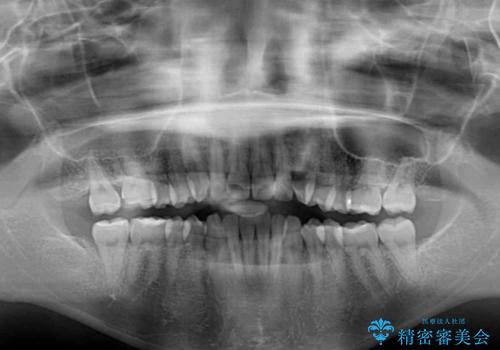

下顎が左側にずれているため、裏側矯正ということもあり咬み合わせを整えるのに時間がかかってしまいました。